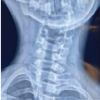

Case one– Twelve year old boy presented to our OPD with difficulty in sleeping in supine position. On examination, a bony hard swelling was detected at the dorsal aspect of right scapula measuring about three into four centimetres. Swelling was fixed to the underlying bone and moved with movement of scapula. Range of movement of shoulder was normal. There was no tenderness around the swelling. X ray of scapula (scapular Y view) showed sessile swelling originating from scapula (Fig. 1). Same thing was confirmed on CT scan of thorax (Fig. 2). Swelling was excised en-mass (Figs. 3 and 4).